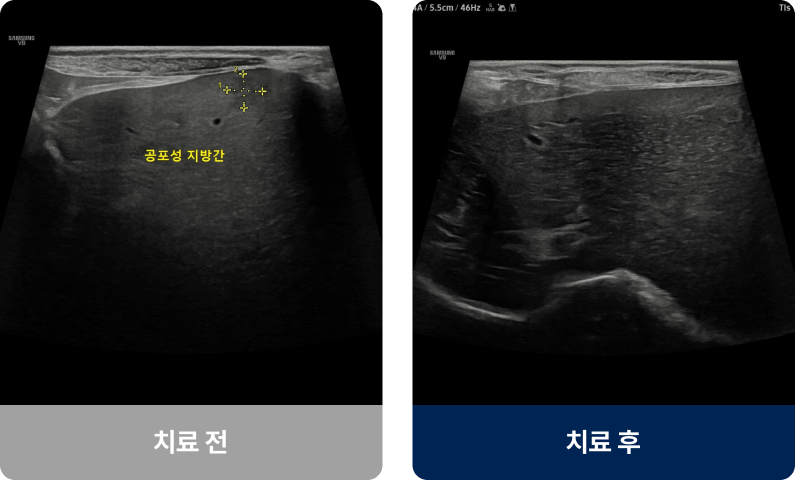

영양 불균형, 약물, 독성물질, 염증, 종양 등의 원인으로 간의 해독과 대사 기능이 저하되는 질환입니다. 주로 중·노령견이나 고양이에게 많이 발생하며 식욕 부진, 구토, 황달(눈·잇몸이 노래짐) 등의 증상이 나타납니다. 진행되면 체중 감소, 복부 팽창, 무기력 등 전신적인 증상으로 악화될 수 있습니다.